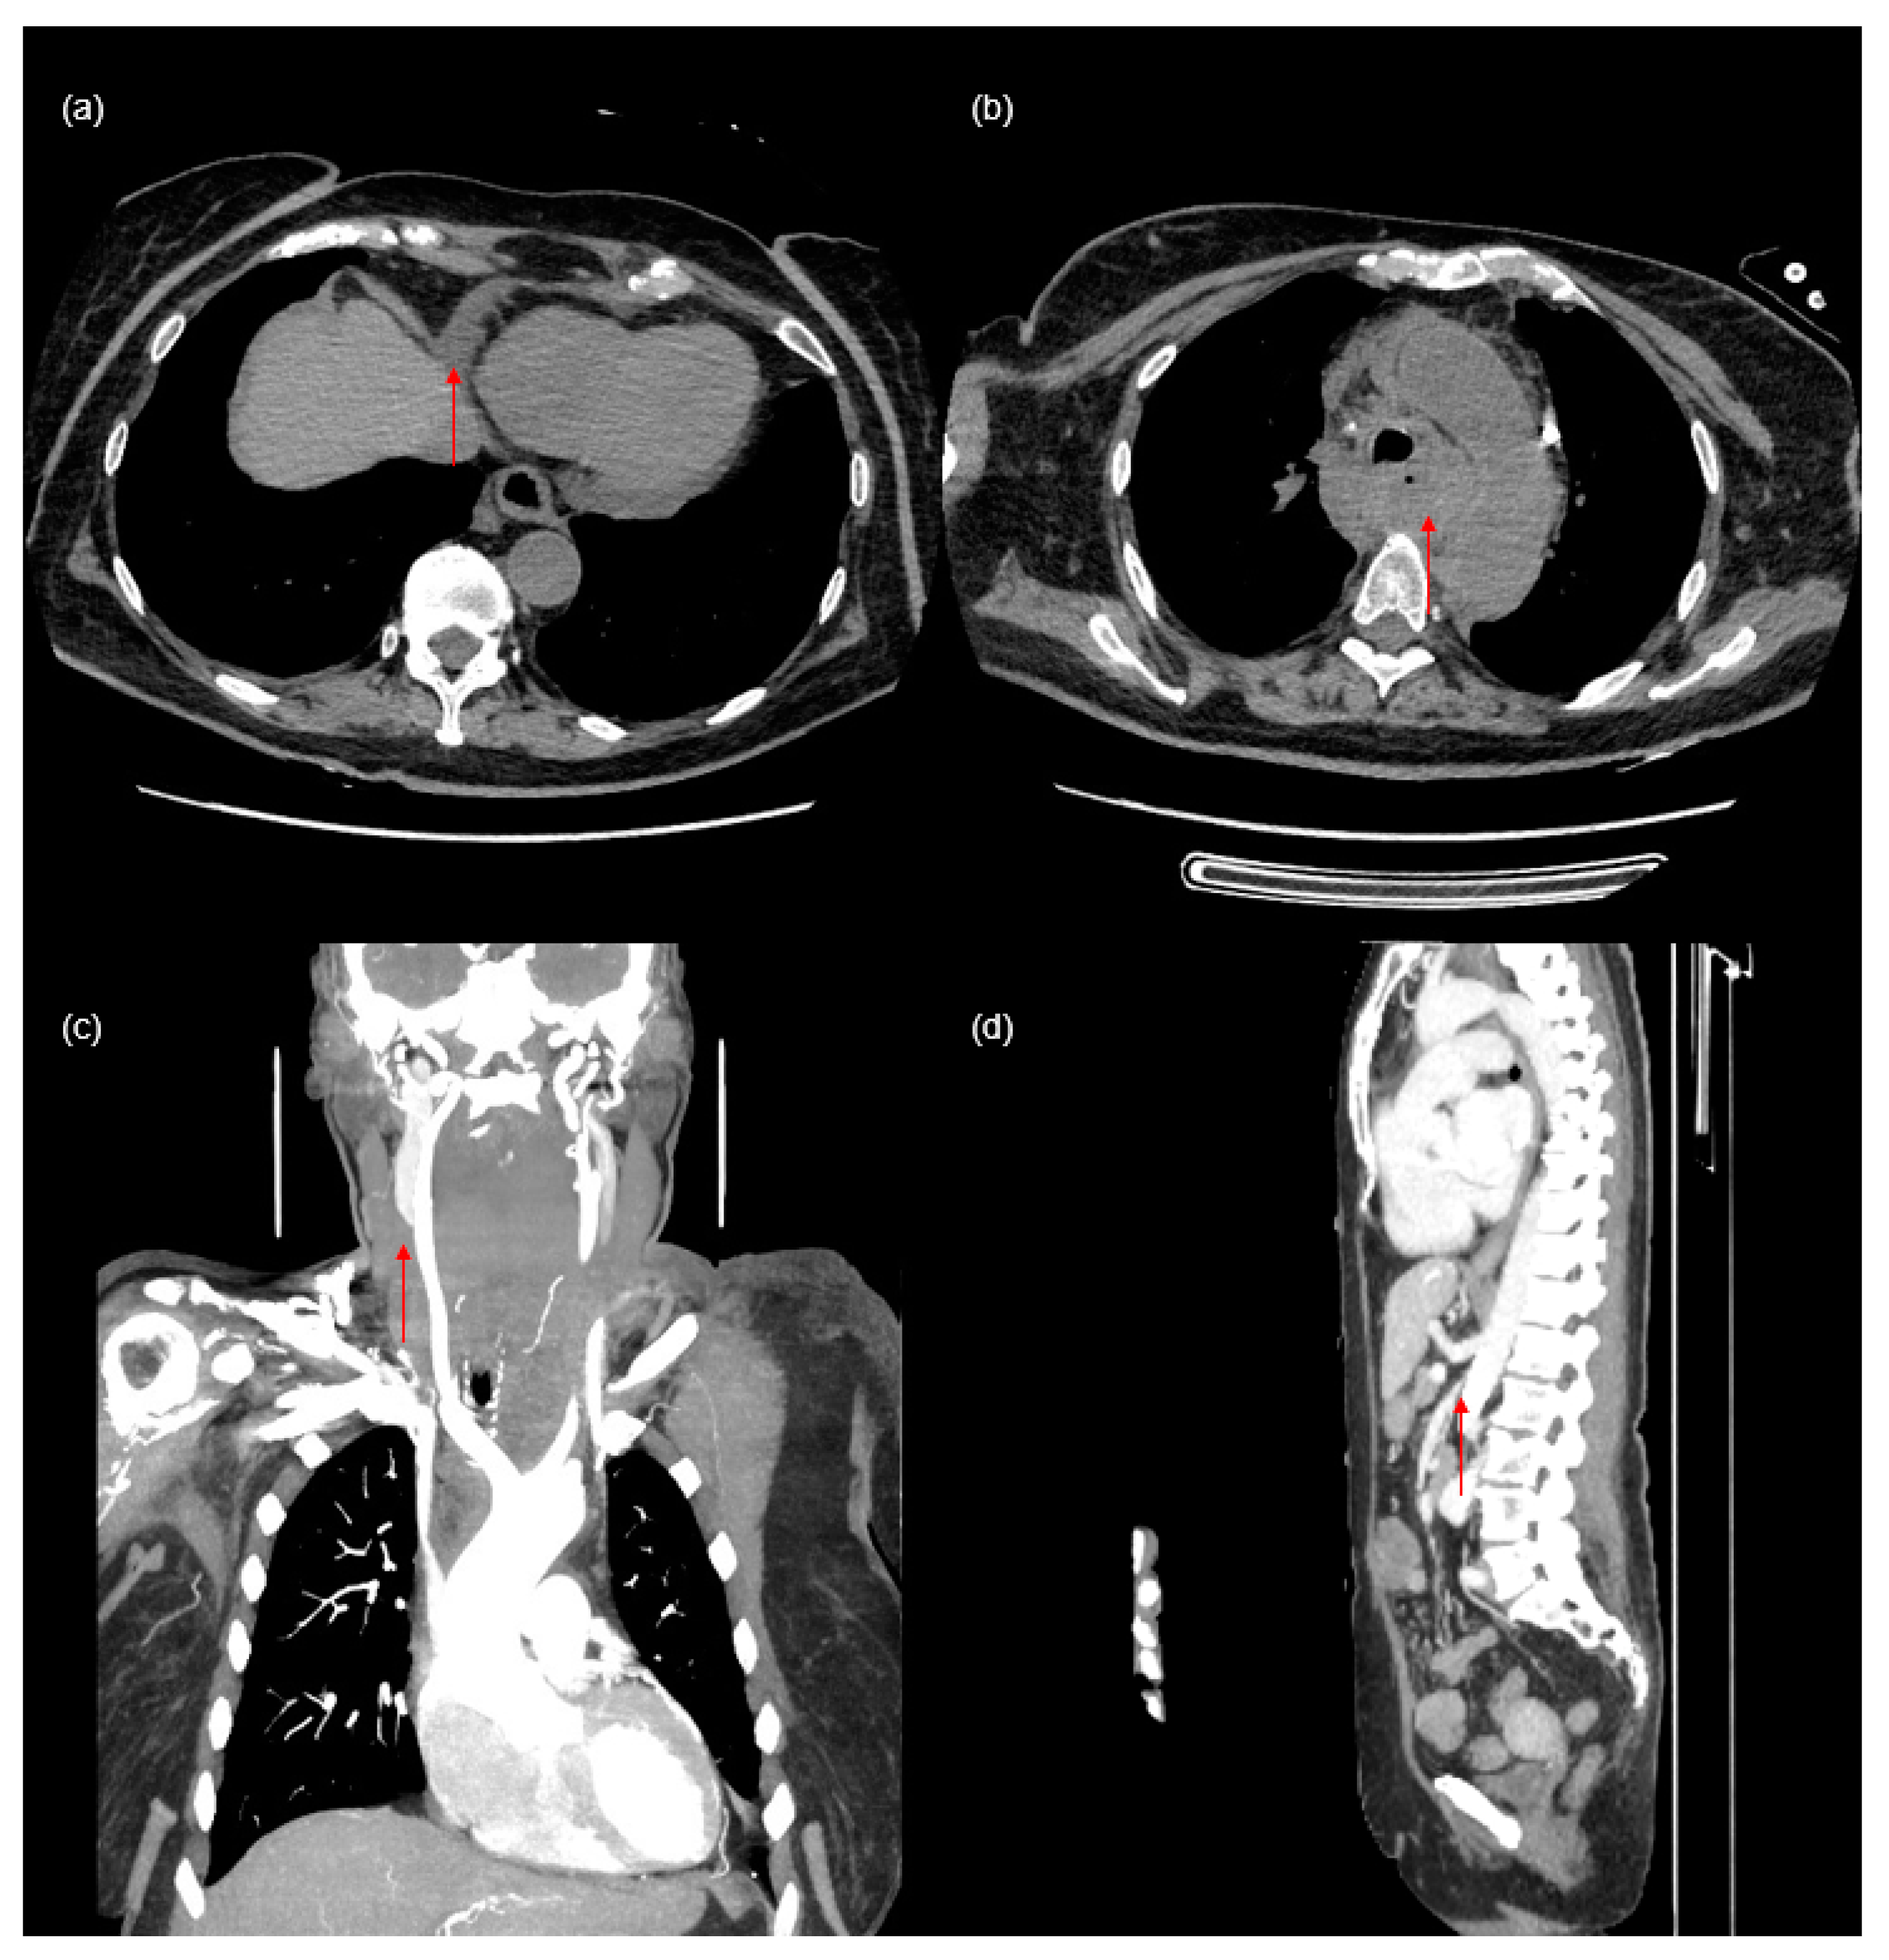

The aim of this report is to present a case of 72-year-old woman with end-stage renal failure due to glomerulonephritis. The patient was admitted to the hospital due to recurrent bleeding from a permanent dialysis catheter placed in the right common jugular vein, possibly caused by mechanical damage thus necessitating replacement. After an unsuccessful attempt to replace the catheter, a secondary catheter was placed in the left jugular vein. Immediately after catheterization, the patient, previously respiratory and circulatory stable, developed swelling of the neck and face. A chest X-ray revealed an abnormal CVC position (

Figure 1a). A computed tomography (CT) study confirmed that the CVC followed a non-anatomical route and was seen on the left side, in the persistent left-sided superior vena cava (PLSVC), and entering in the coronary sinus (

Figure 1b–g).

A small pericardial effusion was detected (

Figure 2a). Additionally, the imaging shows a hematoma in the posterior mediastinum and common jugular vein thrombosis (

Figure 2b,c), which are likely complications of the CVC insertion. The size of the hematoma, which was visible from the foramen magnum to the hiatus of the diaphragm, measured at 53 × 28 × 165 mm. Conservative therapy of the mediastinal hematoma was implemented and was effective in this case.